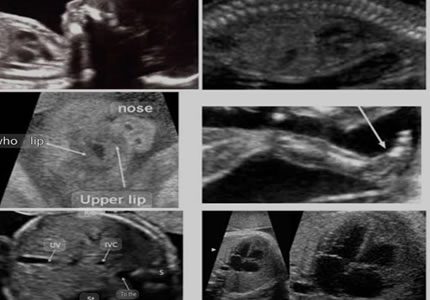

Gender & Mid-Pregnancy Scans (16 – 24 Weeks)

- A thorough "top-to-toe" structural survey of your baby. We systematically evaluate the anatomy—including the brain, spine, heart, and limbs—to screen for developmental markers. This scan offers an in-depth look at your baby's progress during the halfway point of your pregnancy.